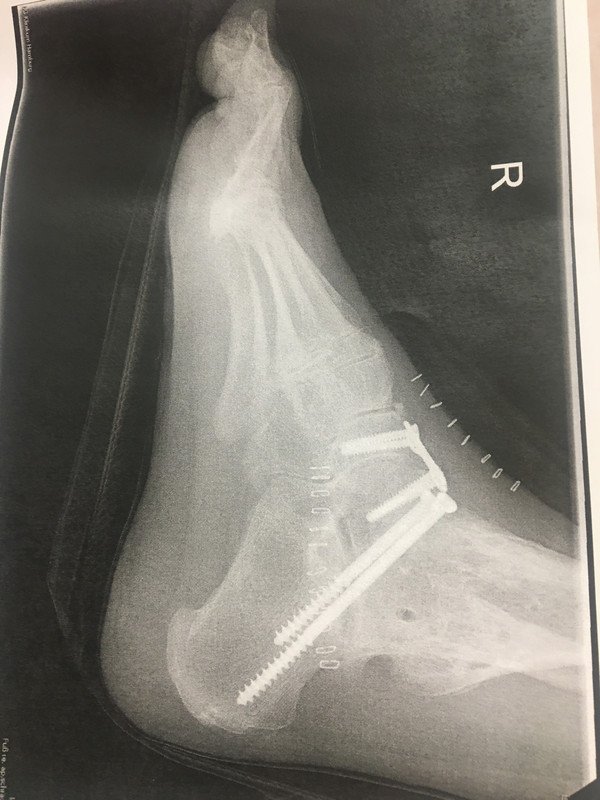

_Monter_ Opublikowano 9 Sierpnia 2020 Autor Udostępnij Opublikowano 9 Sierpnia 2020 Trochę mnie nie było. Ci bliżej mnie wiedzą...a wam opowiem. W jakiś sposób historia się kończy ( w jakiś bo to na pewno nie finał) bo w 2015 pisałem o całkowitym usztywnieniu stawu skokowego no i w styczniu się to stało. Mój staw teraz jest sztywnym kątem prostym bez najmniejszego ruchu....taka literka "L" z nogi. Pochlastali mnie znowu jak szyneczkę. Dopiero co pozwolono mi całkowicie obciążać nogę czyli jej używać. Kwarantannę to ja miałem zanim ktokolwiek wpadł na to z powodu covida...byłem przykuta do wyrka w domu ( i tutaj nadal pojawia się mój uśmiech na twarzy jak ktoś jęczał, ze nie moze dwóch tygodni w domu wysiedzieć) Do tej pory chodziłem jakby w sztywnym bucie narciarskim pod same kolano. Czy ból minął? NIE jest mniejszy, w innych miejscach jednak efektu, na który liczyłem na razie nie widać aczkolwiek za niedługi czas zaczynam rehabilitację pooperacyjną (choc bladego nie mam na czym ma polegać ze sztywnym stawem). Cieszę się, ze nadal mogę chodzić (tylko, ze teraz to juz zupełnie inna bajka i jeśli można nazwać to chodzeniem) a jestem trochę zdruzgotany, że efekty nie są nawet blisko tych jakie były w nadziei. Lewa noga nadal przypomina, ze to tak łatwo się nie skończy. Życiowy wkurw mam nieziemski i tylko Ewa i Maks sprawiają, że oswajam się dość łagodnie z tymi faktami. To w sumie około 15 operacji samej prawej nogi i kilka lewej...Ostatnie 18 miesięcy na zwolnieniu i 3 operacje.Nie ścigajcie się ze zdrowiem i komfortem pełnej sprawności. Nie dostaniecie medalu za coraz szybciej pokonywane zakręty a satysfakcja nie niweluje bólu co stał się codziennością. Wrzucę ponownie foty bo photobucket wyjebałem z powodu ich pazerności. Tutaj ostatnie: Tutaj stare: Link do trasy:https://goo.gl/maps/bi2UVt3bPGQFGBnT8 Foty motóra i barierek:https://postimg.cc/gallery/t4VHk2p (cała galeria) Dzięki Minolci, która namierzyła miejsce i google uwieczniło wygiętą barierę małe kółko to moja pozycja a duze kółko to pozycja kufra centralnego. Możecie negować po raz enty, że to opisuję ale jeśli choć jeden z was zwolni przed winklem to uważam, że warto było. Cytuj lewa noga: http://forum.motocyk...__1#entry782383 prawa noga: http://forum.motocyk...__fromsearch__1...i tak wszyscy umrzemy... Odnośnik do komentarza Udostępnij na innych stronach Więcej opcji udostępniania...